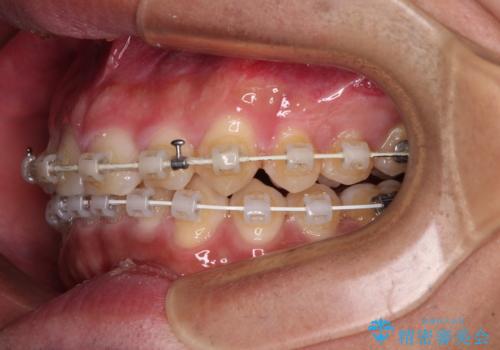

深い咬み合わせと隙間の空いた歯列をワイヤー矯正で改善

- 前歯の隙間と深い咬み合わせを改善したいとのことで来院された患者様です。

マウスピース矯正の自己管理が面倒とのことで、ワイヤー矯正により治療を行うこととしました。

奥歯の咬み合わせは理想的な状態であったため、ワイヤー矯正でもインビザラインでも比較的容易に対応可能でした。